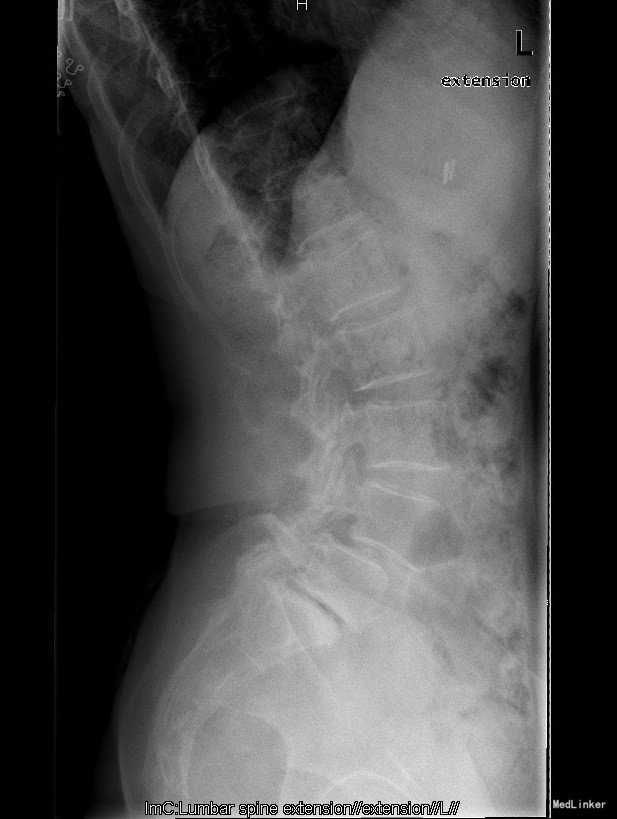

主诉:反复腰部疼痛20+年,加重伴双下肢胀痛麻木 现病史:患者于20+年前,因车祸行腰椎检查发现腰4椎体I°滑脱,并感腰部阵发性隐痛不适,一直未行特殊处理、4月前患者感腰部疼痛有所加重,并感双下肢阵发性胀痛麻木,久坐或弯腰后症状加重,以左下肢为甚,症状明显时难以直立行走,不伴畏寒发热、潮热盗汗等不适。10+天前患者在院外行理疗(具体不详),上述症状略有好转。在院外行腰椎x光摄片诊断为"腰4椎体II°滑脱,腰5椎体I°滑脱",故来我院就诊,门诊以"腰椎滑脱"收入住院

查体:脊柱外观无侧弯后突畸形,双下肢无肌肉萎缩。腰4-5、腰5骶1棘上棘旁轻压痛,伴左侧下肢放射;会阴部感觉未见异常,双侧小腿前外侧及足背足底感觉减退。腰椎前屈后伸及侧屈活动度正常;双下肢髂腰肌肌力4级,左侧直腿抬高试验阳性,加强试验阳性,左侧膝腱反射减弱,双侧病理征未引出。 辅助检查:院外腰椎正侧位片:腰4椎体II°滑脱,腰5椎体I°滑脱。

诊断:腰4椎II°滑脱症,腰5椎I°滑脱症 治疗:经后路腰4、5椎切开复位、椎管减压、Capstone椎间及后外侧人工骨+自体骨植骨融合、Legacy内固定术